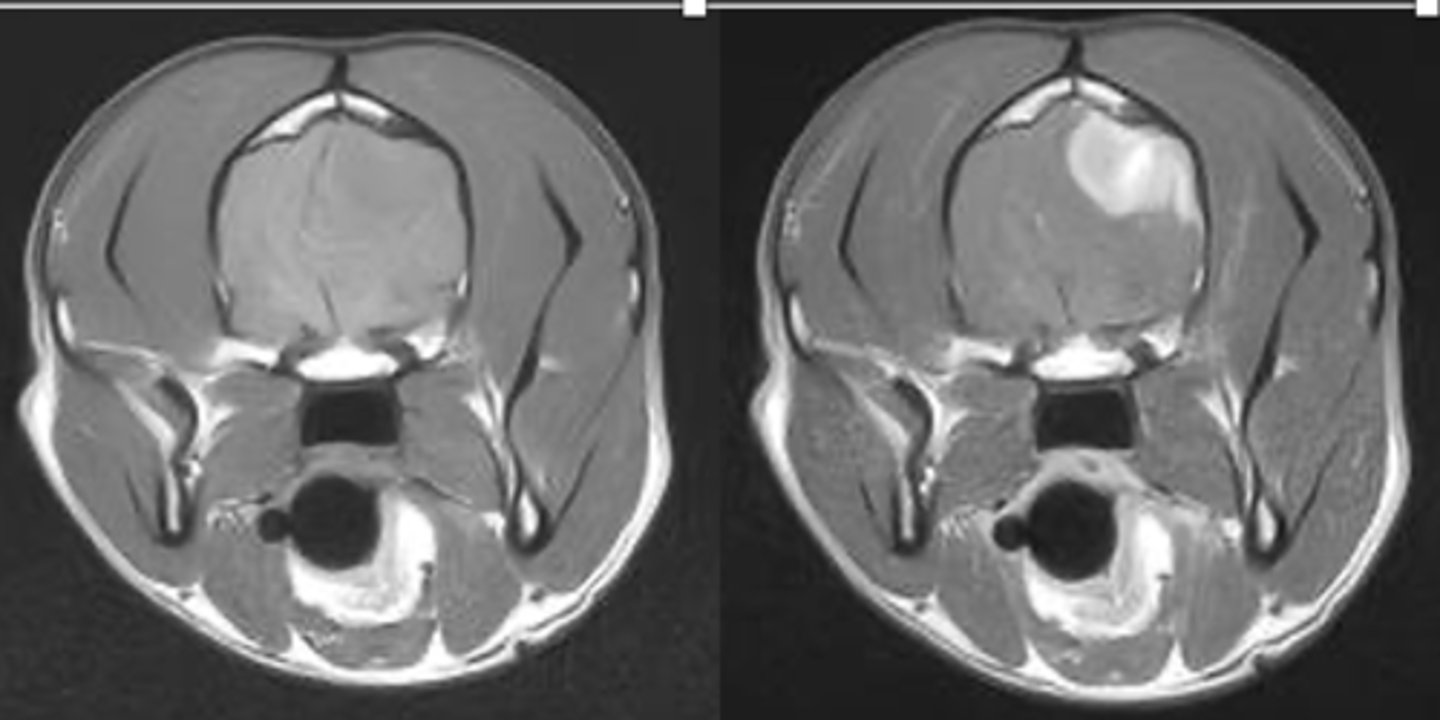

left- pre contrast

right- post contrast

which MRI is pre and post contrast?